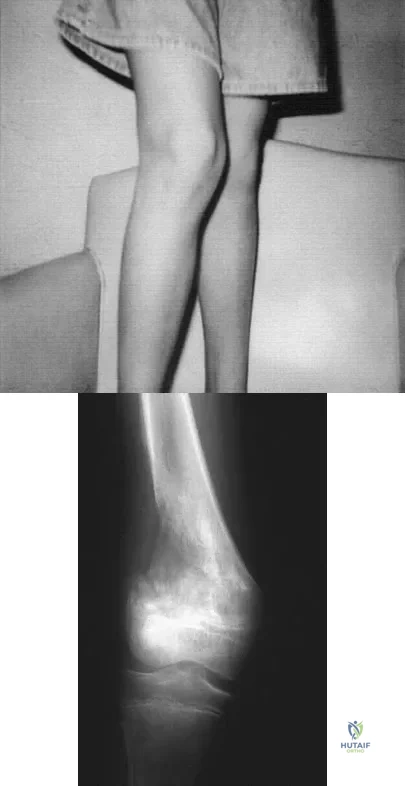

A 13-year-old patient has foot drop and lateral knee pain. AP and lateral radiographs and an MRI scan are shown in Figures 49a through 49c. A biopsy specimen is shown in Figure 49d. What is the preferred method of treatment?

Explanation